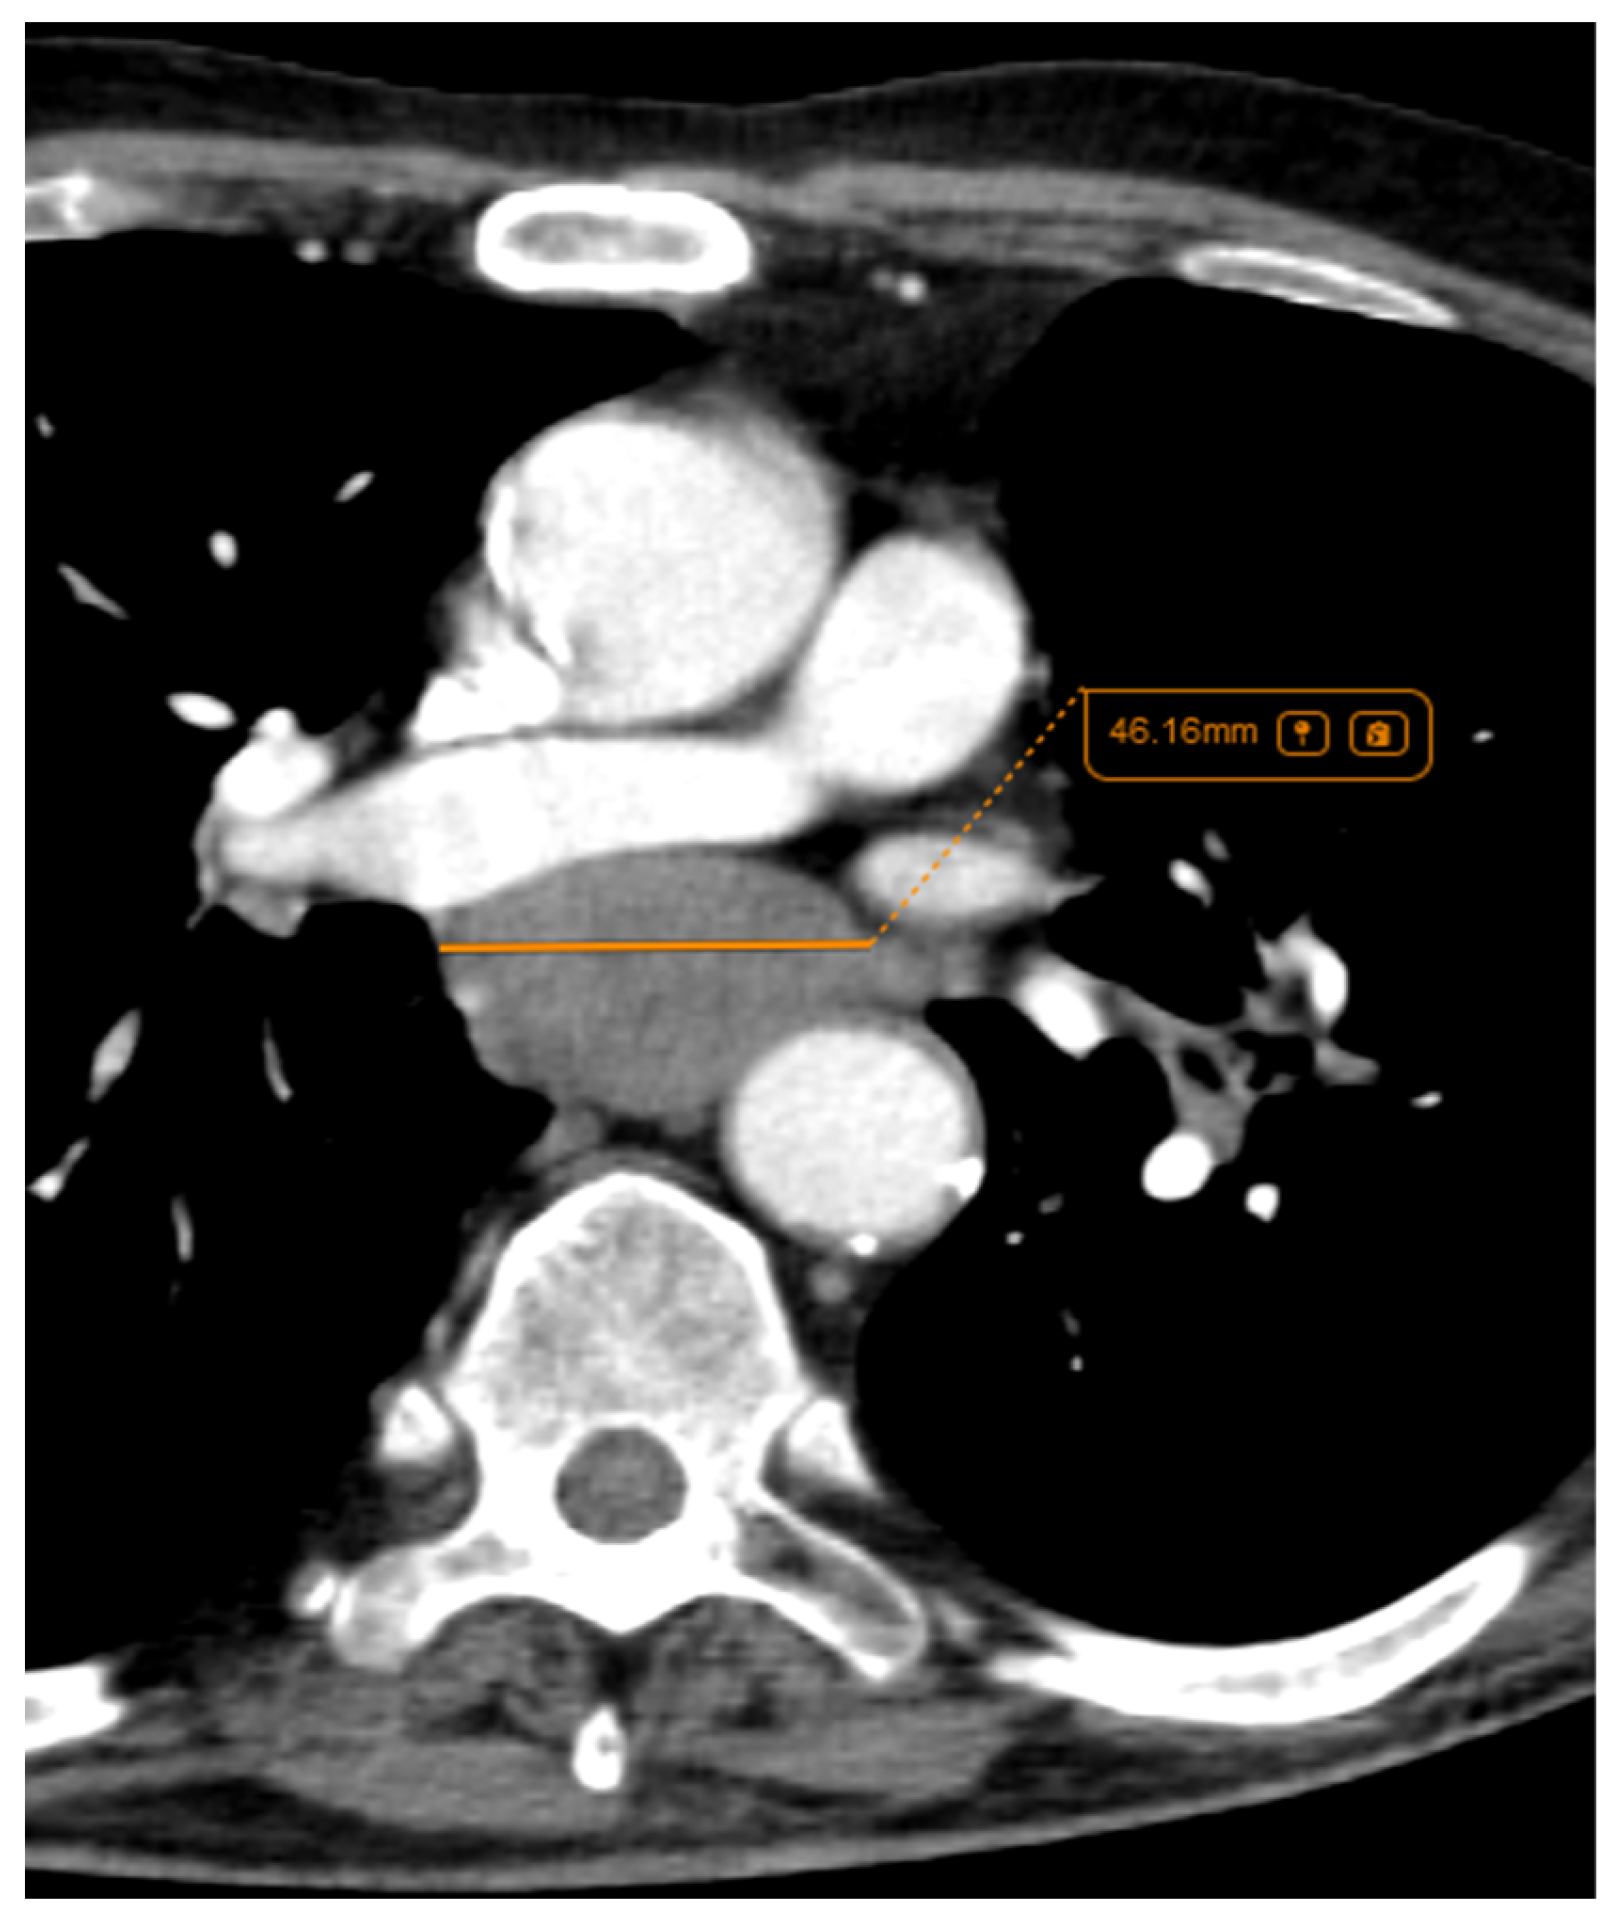

Considering the exclusion criteria previously mentioned, a total of 58 patients were analysed in this study, in which 26 cases were pathologically proven to be adenocarcinoma (Figure 1), 22 cases were shown to be squamous cell carcinoma (Figure 2), and 10 cases were shown to be small cell lung cancer (Figure 3).

Figure 2.

Axial CT of two different cases of squamous cell carcinoma: (A,B) show a right hilar mass with cavity and air bubbles inside, with invasion of the hilar vessels and right main bronchus extending over less than 2 cm from the carina; and (C,D) show a left hilar mass with atelectasis, necrosis, septal thickening, and important invasion of the pulmonary trunk and left pulmonary artery.